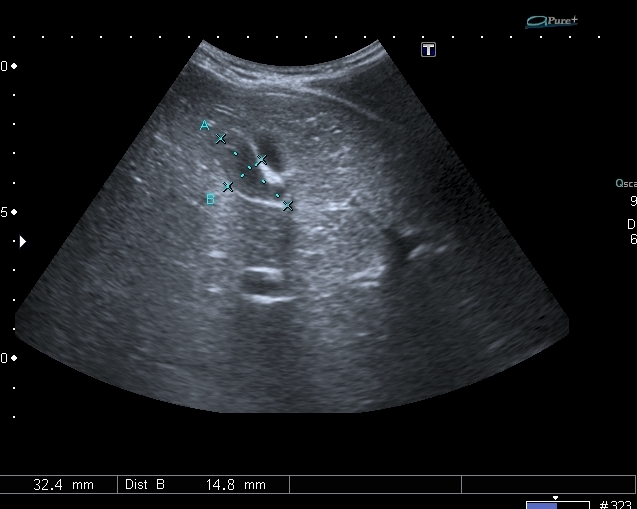

На УЗИ рядом с желчным пузырём определяется овоидное образование солидной струкутры с чёткими контурами.

При ЦДК кровоток в образовании не регистрировался, свободной жидкости в брюшной полости не было.

Предположил наличие удвоения желчного пузыря, с этим заключением пациент исчез из поля зрения.